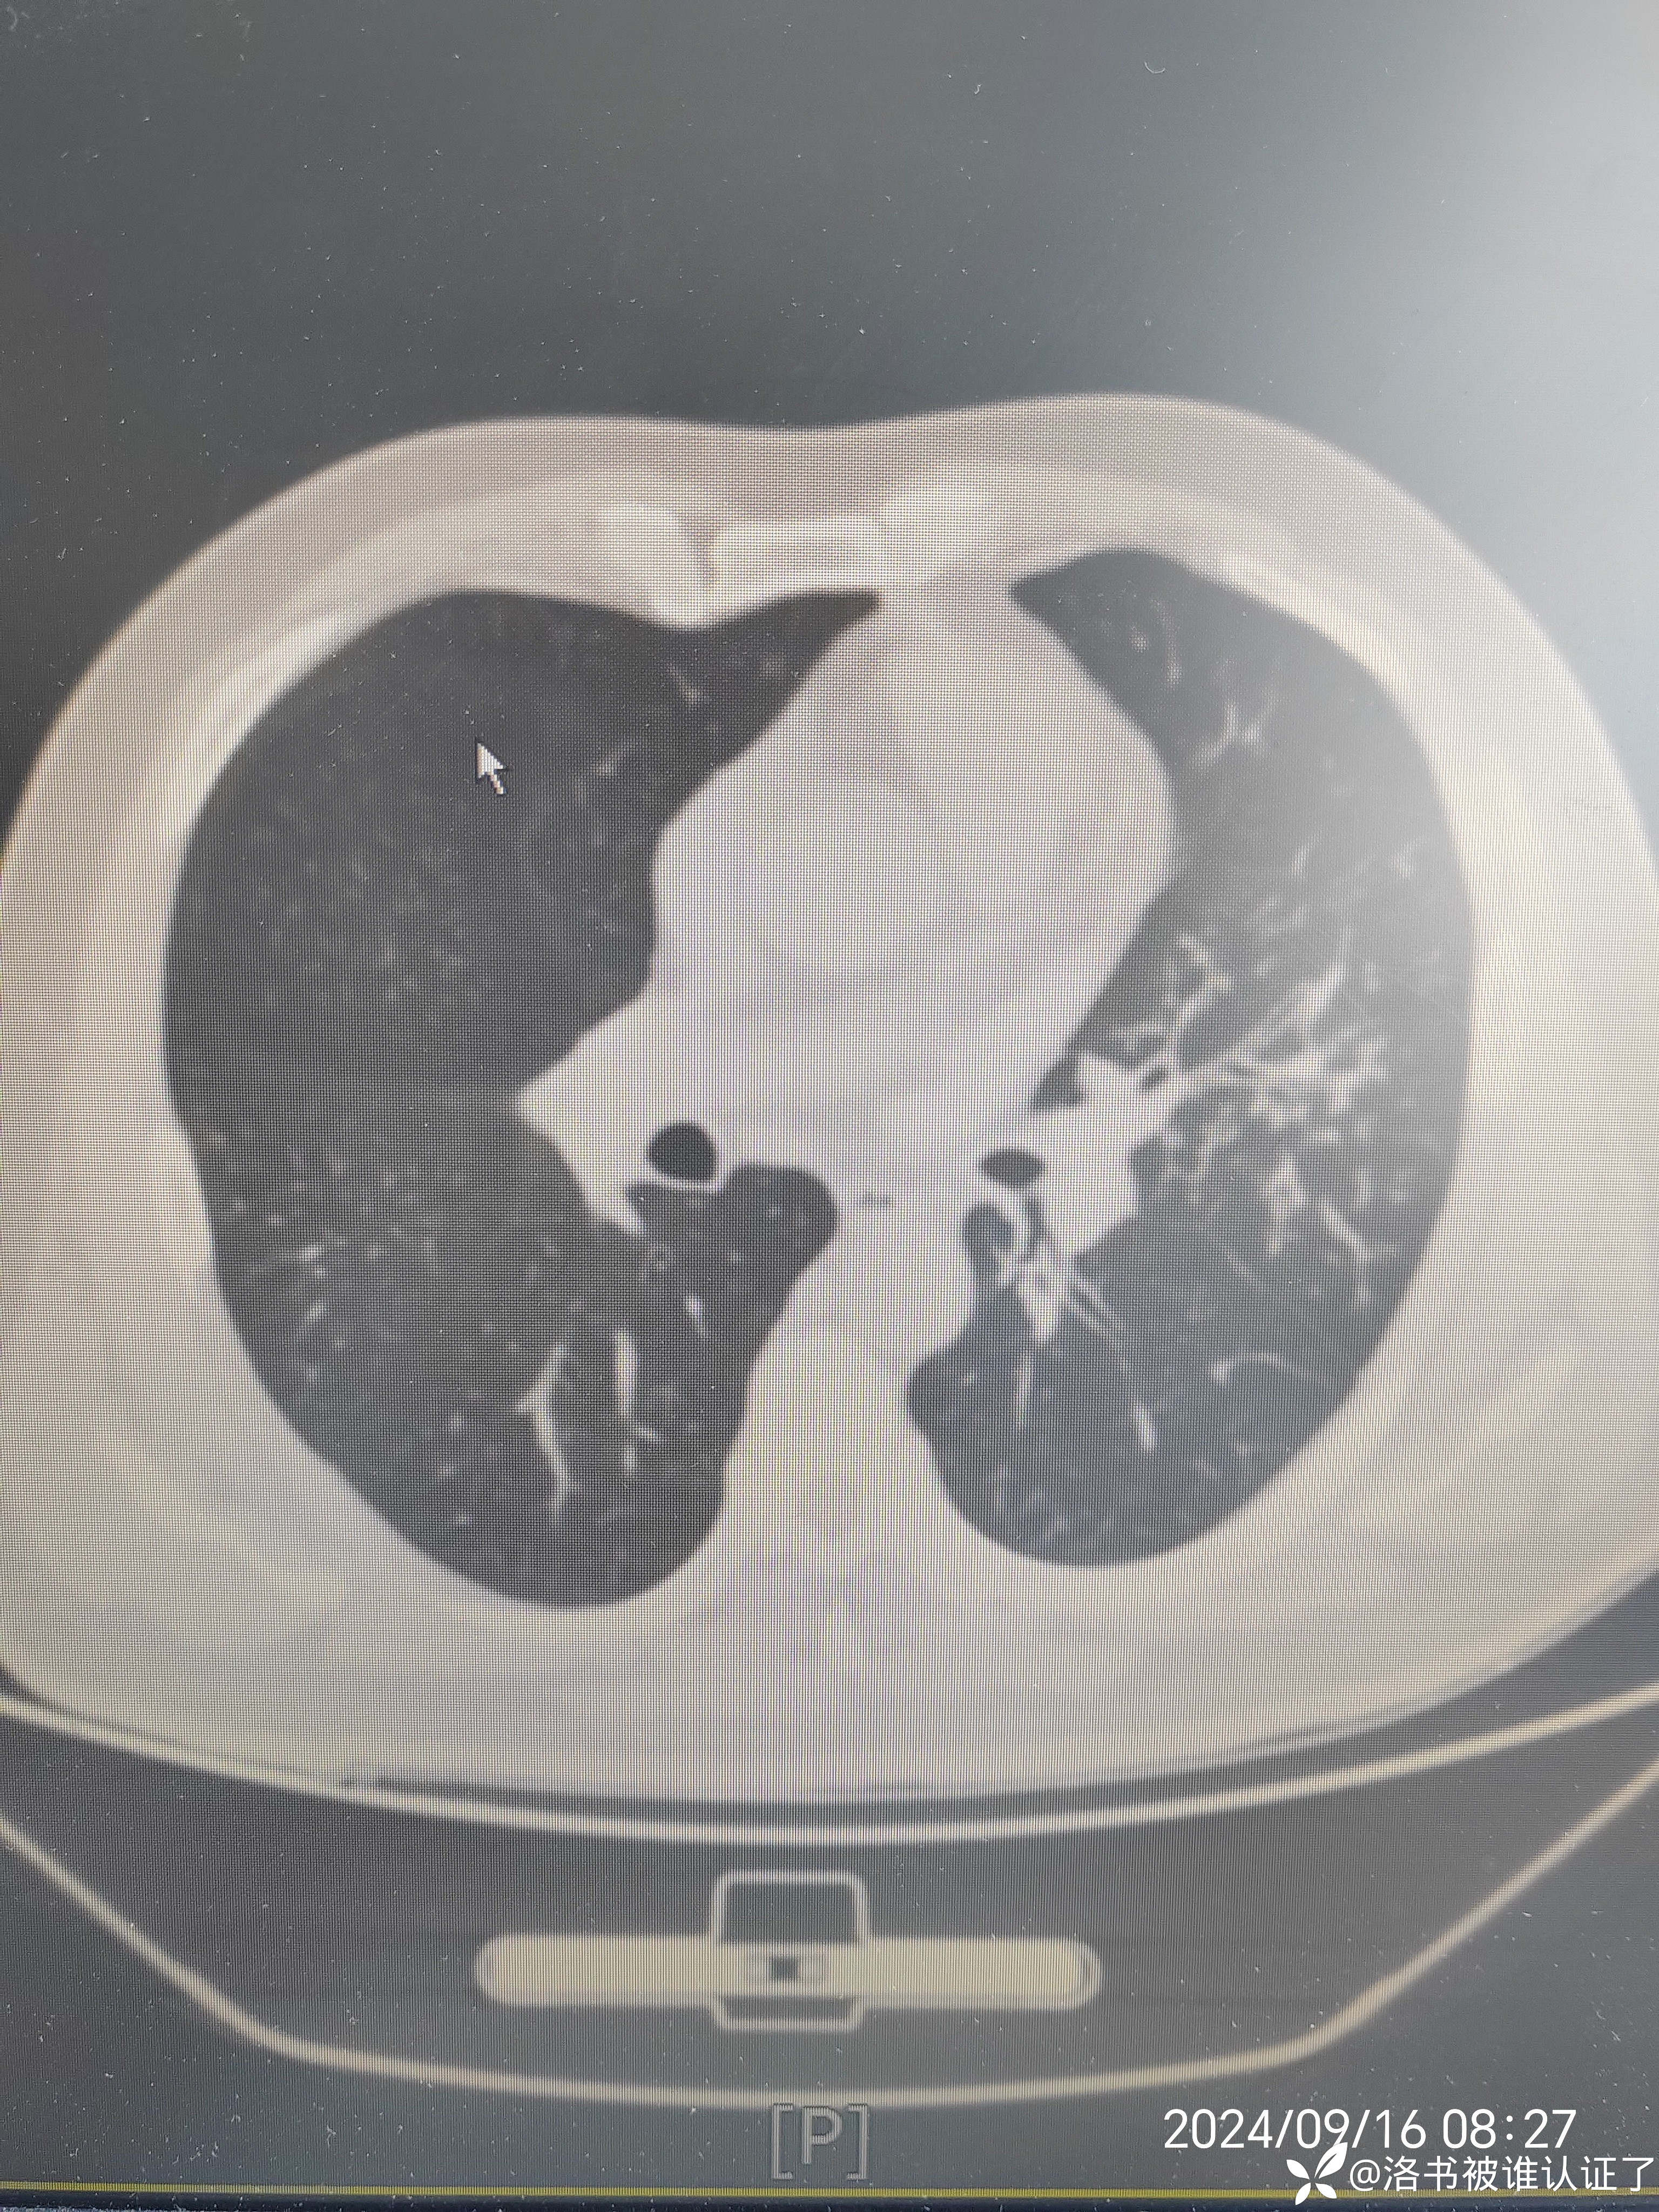

【检查】胸部CT示肺炎。

【临床诊断】:肺炎